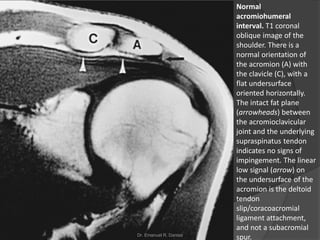

Normal

acromiohumeral

interval. T1 coronal

oblique image of the

shoulder. There is a

normal orientation of

the acromion (A) with

the clavicle (C), with a

flat undersurface

oriented horizontally.

The intact fat plane

(arrowheads) between

the acromioclavicular

joint and the underlying

supraspinatus tendon

indicates no signs of

impingement. The linear

low signal (arrow) on

the undersurface of the

acromion is the deltoid

tendon

slip/coracoacromial

ligament attachment,

and not a subacromial

spur.